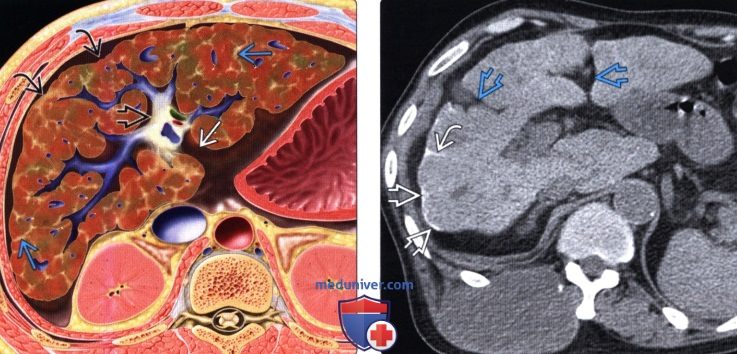

Методы динамического контрастирования печени на МРТ

Раздел: Снимки-подсказки